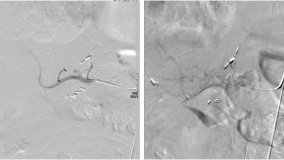

With invasive techniques, a catheter – a long, thin, flexible tube – is inserted into a peripheral artery and threaded to the heart. Through this catheter, a contrast media is injected into the blood stream, following which X-rays are used to take pictures of the heart’s anatomy and the arteries that bring blood to the heart muscle to assess the degree of their openness, also called patency.

This procedure, called cardiac catheterization, is the "gold standard" to evaluate the cardiac anatomy and the severity of a physiological dysfunction. It is recommended for various reasons, the most common of which is to evaluate chest pain. However, its wide usage is limited by its invasive nature.